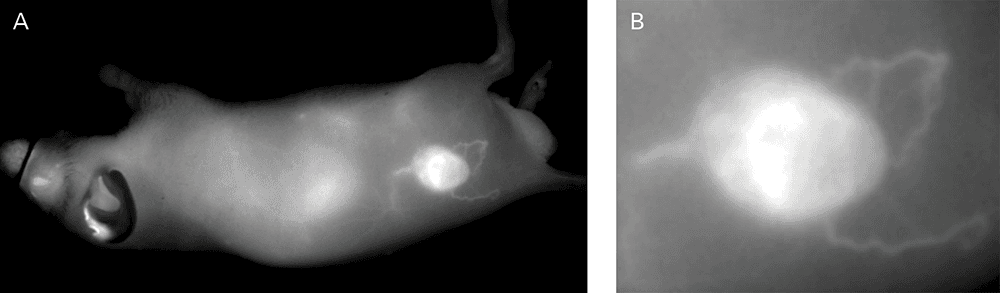

An NIR dye-conjugated contrast agent, such as IRDye 800CW PEG (polyethylene glycol), serves as a non-specific contrast agent for vascular imaging. The labeled agent is administered to mice intravenously (IV injection) and highlights surface vasculature for 30 minutes post-injection (Figure 6). The retention of the agent is visible in the tumor 4 hours post-injection (Figures 7A, B; requires appropriate mouse model*) and the tumor region is defined by 9 hours post-injection (Figure 8).

*Success of vascular imaging depends on the mouse model used. Vessels may be less visible in mice that are obese or have hair.